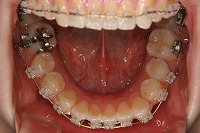

下顎

23歳5か月